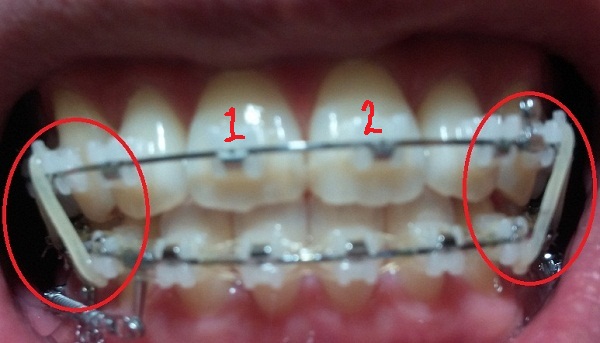

치료내용

-하악 파워체인 엇갈려서 걸어놓기(후기 23화와 같은 치료),

-하악 스프링 + 덧대기(잇몸이 눌리지 않게)

-고무줄착용하기(전 치료와 동일)

현재 교정진행상태

-중심선 99% 맞은 상태!!

-하악 파워체인으로 치아끼리 꽉 조여서 마무리로 가는 중!!

-일회용 고무줄로 치아를 다물 때, 뜨는 공간이 없게

상악 송곳니와 하악 송곳니를 당기는 중!!

[정면]